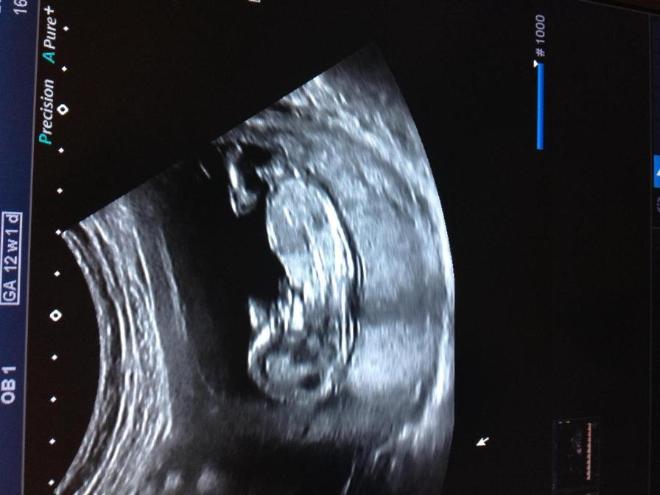

11,6 недель и как видно мальчишечку! (Под кат)

Вот! Я бы сама и не разглядела, врач и опытные мамочки сразу увидели наше достоинство :) А вам видно?

У меня есть две мамочки у одной 6 деток, другая ждет 5-ую, они сразу увидели! О как :) Я увидела, если пальцем тыкнуть. На животике пуповина а ниже торчком это то что определяет пол :)